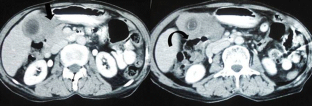

Of the 566 patients with GB mass and suspected GBC, 239 were found to be inoperable on preoperative workup and 129 patients had unresectable disease on staging laparoscopy/laparotomy. Of the 198 with resectable disease, 31 were reported as XGC on final histopathology (Group A), while 167 were GBC (Group B). Of these 31 patients, six with an intraoperative suspicion of benign pathology underwent cholecystectomy with segments IVb and V resection, and frozen section histopathology. Twenty-five underwent radical cholecystectomy, with (n = 10) or without (n = 15) adjacent organ resection. In comparison, anorexia and weight loss were significantly more in Group B (p = 0.001 and <0.001). Intraoperatively, empyema and associated gallstones were more common in Group A (p = 0.011 and <0.001). On computed tomography (CT) of the abdomen, continuous mucosal line enhancement and intramural hypodense bands were significantly more in Group A (p < 0.001 and 0.025). While CT abdomen revealed one or more features suggestive of XGC in 64.5 % (20/31) of patients in Group A, 11(35.5 %) did not have any findings suggestive of XGC on imaging.

Mass-forming XGC mimics GBC, making preoperative and intraoperative distinction difficult. While imaging findings can help in suspecting XGC, definitive diagnosis require histopathological examination. Presence of typical radiological findings, however, can help in avoiding extended radical resection in selected cases.

Fig. 2